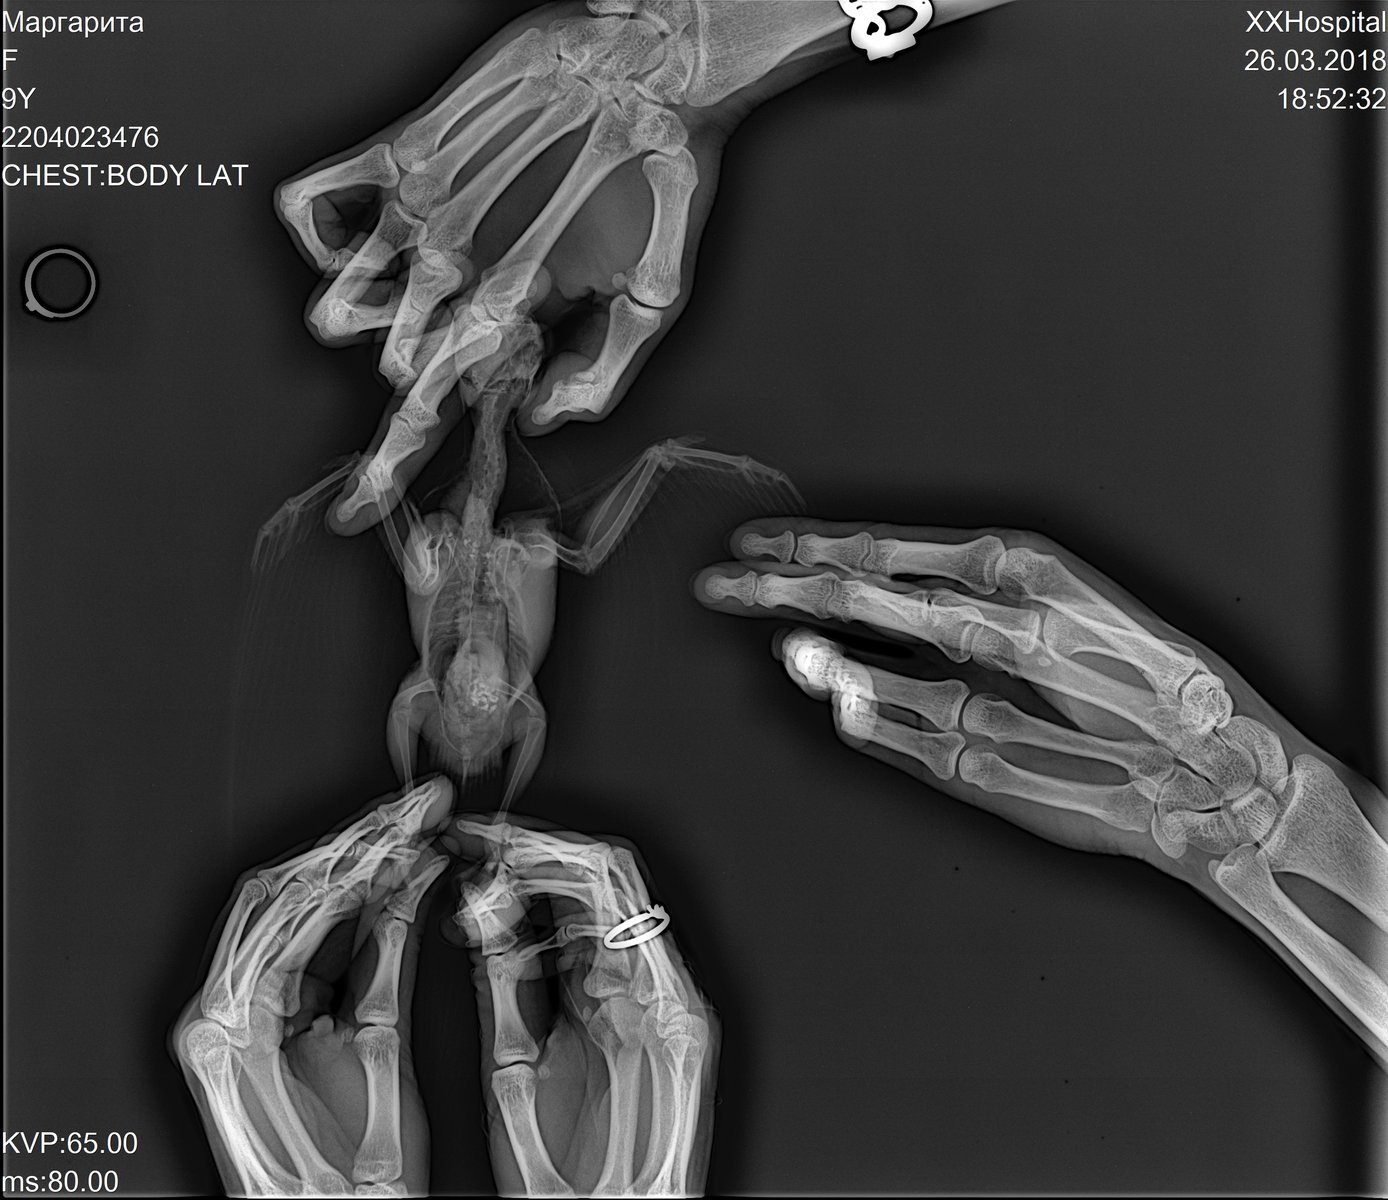

OlgaVoevodina Опубликовано 26 марта, 2018 #94 Опубликовано 26 марта, 2018 Здравствуйте, сегодня ходили на рентген. Корелла, 9 лет. Продолжительное время был синусит, долго лечили. Недавно обнаружили вздутые воздуховодные мешки, решили отвести на осмотр. Врач поставила диагноз грибковая пневмония. Сказала, в худшем случае - аспергиллез. Сказали, взять анализы крови, смывов на бак посев, микологию и цитологию. А так же бронхоскопия/целиоскопия. Но все это под наркозом, в два этапа...Подскажите, пожалуйста, как кореллы переносят наркоз? Птица активная, но чихает, воздуховодные мешки и глазки опухшие. Прилагаю фото рентгена.

Pavel Z Опубликовано 18 марта, 2019 #107 Опубликовано 18 марта, 2019 Я так понимаю, в этой ветке бывают опытные врачи. Хотелось бы проверить диагноз врача по рентгену. И пока я не описал ситуацию и не выложил снимки... мало ли кто прочитает из специалистов. Врач сказала, что нельзя начинать антибактериальную терапию раньше, чем противогрибковую, потому что грибы тут же попрут. Правда? И еще, насколько работают имуномодуляторы и гепапротекторы. Доказан ли эффект? Пеленать жако дважды в день, как я видел сегодня (поначалу было страшно) и вливать ему по несколько лекарств... ведь каждое лекарство вливается несколькими порциями с поглаживанием по горлу птицы и при этом он ворчит вырывается пищит... это испытание. Снимки тут можно выложить?

Pavel Z Опубликовано 18 марта, 2019 #108 Опубликовано 18 марта, 2019 Жако, самец, 6 лет. Прослушивание показывает хрипы при дыхании. Сделали снимки в двух проекциях, клинический анализ помета. Ссылки на снимки прилагаю в конце. По анализу помета, есть вопросы в трех местах: кишечный эпителий +++, лейкоциты - единично, палочки - 30%, остальное в норме. Мазок не бралии странно, не вижу в бумаге диагноза.. На словах Волгина сказала есть основания считать аспергиллез. Назначено: - вифенд 2 раза в день ГОД (!!!) - или тербинафин с подбором дозировки 2 раза в день ГОД (!!!) - суммамед суспензия 2 раза в день, 30 дней - Гептрал 1 раз в день год - Иммунофан 1 раз в день (не привожу описаний приготовления, дозировки, вспомогательное) Вопросы: - где на снимке видны проблемы и можно ли сказать что четко аспер? - действительно ли нельзя начинать антибактериальную терапию до антигрибковой? (грибы начинают быстро расти?) - много шансов на излечение в принципе? (лечить буду конечно!) - насколько эффективны эти гепатопротекторы и иммуностимуляторы? (я видел и пробовал эту процедуру вылова птички, пеленания, захвата головы, вливания шприцем по частям с поглаживанием - это надо долго держать будет...) - слышал подделывают вориконазол - были случаи? Снимки https://mega.nz/#!bNowDCYC!6jfCV5Htlnw6TsVnuddn2HVlJTpmqiMC5_91X-49pIs https://mega.nz/#!ychAHIwA!bb0yDuZcFyLwMQ2YnHYPdKxxWpO0RVnRx_5Rp11UgqY

Pavel Z Опубликовано 19 марта, 2019 #114 Опубликовано 19 марта, 2019 Надо было просить описание снимков, хотя может врач и сделала, я позвоню. Мне знающие люди указали куда смотреть. На снимках в подключичных мешках есть гранулемы и совсем чуть чуть какие то вкрапления в правом легком. Чтобы сказать точно, что это аспер, нужно сделать мазок. Странно, что такой специалист как Волгина С.В. об этом не сказала ровным счетом ничего. Но ясно точно, что нужна антибактериальная терапия и проводить ее нужно с антимикотиком. И тут очень важный вопрос, в виду ДИКОЙ стоимости вориконазола в сочетании с вероятностью купить подделку: можно ли провести а\б с тербинафином и по результатам принять решение о вориконазоле? Антибактериальная нужна, хрипы при дыхании при прослушивании врачом. До Волгиной тоже попробую достучаться сегодня.